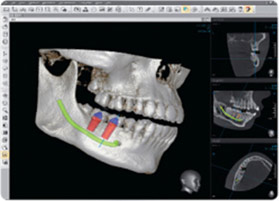

Planificación y realización mejorada de implantes

La radiología dental le permite mejorar la planificación del tratamiento y obtener resultados superiores